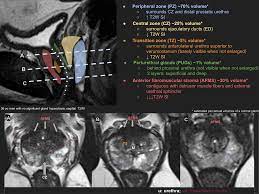

Https Epad Uroweb Org Wp Content Uploads 3 Role Of Mri J Barentsz Pdf

Https Epad Uroweb Org Wp Content Uploads 3 Role Of Mri J Barentsz Pdf from